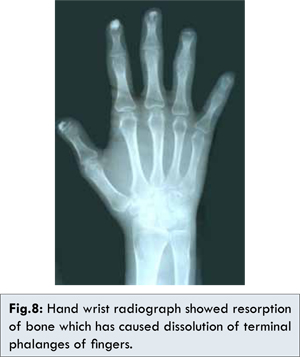

Patient was then subjected to radiographic examinations and OPG radiograph showed generalized widening of the periodontal ligament space, with bony resorption (irregular) on posterior border of coronoid process on both right and left side and resorption of inferior border, posterior border of ramus and angle of mandible on right side [Fig. 6,7]. Hand wrist radiograph showed resorption of bone which has caused dissolution of terminal phalanges of fingers [Fig. 8].

Radiographically, this patient showed generalized widening of periodontal ligament space, with bony resorption (irregular) on posterior border of coronoid process on both right and left side and resorption of inferior border, posterior border of ramus and angle of mandible on right side. Hand wrist radiograph showed resorption of bone which as caused dissolution of terminal phalanges of fingers.